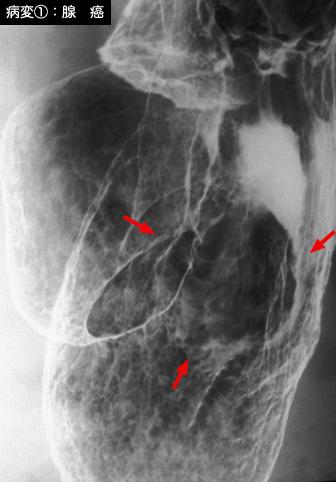

疾患(病理主体)の分類悪性上皮性腫瘍/腺癌

部位(臓器別)胃(部位)/体部

検査方法X-P

腫瘍の肉眼分類0型(表在型)/IIa型(IIa+IIc)

病変の最大径(ミリ)25〜29

腫瘍の深達度sm